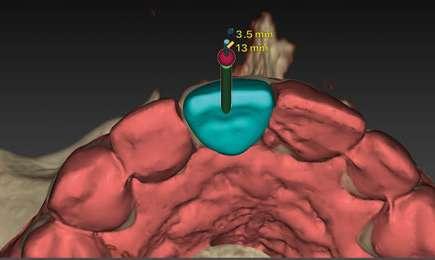

Todos sabemos que el aspecto más crítico a la hora de realizar un tratamiento implantológico y de obtener un buen resultado es sin duda la posición 3D de nuestro implante.

Para ello es imprescindible tener bajo control todas aquellas variables que pueden influir en dicha posición tal como la proximidad a dientes vecinos, margen de la futura restauración, volumen de hueso existente, emergencia protética, profundidad del implante, aditamentos protéticos.… Un sinfín de factores a tener en cuenta en los cuales las herramientas digitales van a jugar un papel crucial al permitir, controlar todos esos aspectos antes de abordar el caso, pudiendo verificarlos y cambiarlos, incluso antes de afrontar la cirugía.

Para manejar todos estos datos vamos a necesitar de un software de diagnóstico y planificación digital como es el de DTX StudioTM Implant en el cual vamos a abrir tanto el CBCT como el escaneado intraoral y nos va a permitir fusionar ambas mayas utilizando la herramienta SMARTFUSION. En un caso como éste, donde tenemos un incisivo central, superior, derecho, fracturado que vamos a extraer debemos realizar previamente la extracción Virtual en el modelo digital para poder incorporarlo a la planificación de nuestro software.

Con todos estos datos fusionados en el DTX StudioTM Implant, lo que vamos a hacer es utilizar la función SMARTSETUP para tener un encerado Virtual que nos permita determinar la posición de la futura restauración del paciente, en función de la cual colocaremos nuestro implante y el aditamento más adecuado.

En este caso, podemos ver que tenemos un defecto óseo vestibular, se trata de un defecto de una sola pared de la zona a implantar. Intentamos planificar un implante inmediato y observamos la posibilidad de tener un buen anclaje apical por lo tanto nuestra primera opción va a ser la realización de un implante post extracción con regeneración de la pared vestibular mediate xenoinjerto óseo e injerto de tejido conectivo para mejorar el biotipo.

En el caso de obtener suficiente torque, podríamos incluso valorar la opción de cargar dicho implante. En este caso lo que hacemos es planificar también un pilar con el fin de trabajar nuestra prótesis a nivel gingival, siguiendo la filosofía de “One Abutment-One Time (OAOT)”.

Lo realmente extraordinario de este software de diagnóstico y planificación es que en una sola imagen tenemos total control de la posición de nuestro implante y de nuestro pilar, en función del hueso de la encía y de la futura restauración. Por lo tanto vamos a realizar una implantología protética, y biológicamente guiada.

Planificación

Una vez tenemos todos los datos, decidimos como primera opción realizar una cirugía guiada post extracción con regeneración y carga inmediata.

Otra de las ventajas que nos ofrece el software de diagnóstico y planificación DTX StudioTM Implant es la posibilidad de diseñar una férula quirúrgica y exportarla con el fin de poder imprimirla de manera local y acortar así los tiempos de preparación.

10.- Colocamos implante Nobel Biocare N1TM TiUltra de 3,5x13.